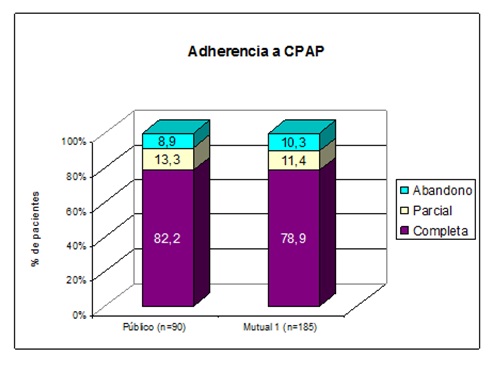

Para evaluar la adherencia a la CPAPn fue posible seguir durante un año a 90 pacientes del sector público y 185 del sector privado. La adherencia al tratamiento fue la siguiente: adherencia completa (> 5 horas de uso por noche) = 82,2% y 78,9%; adherencia parcial (< 5 hs/noche) = 13,3% y 11,4% y abandono del tratamiento= 8,9 % y 10,3% (Figura 14).